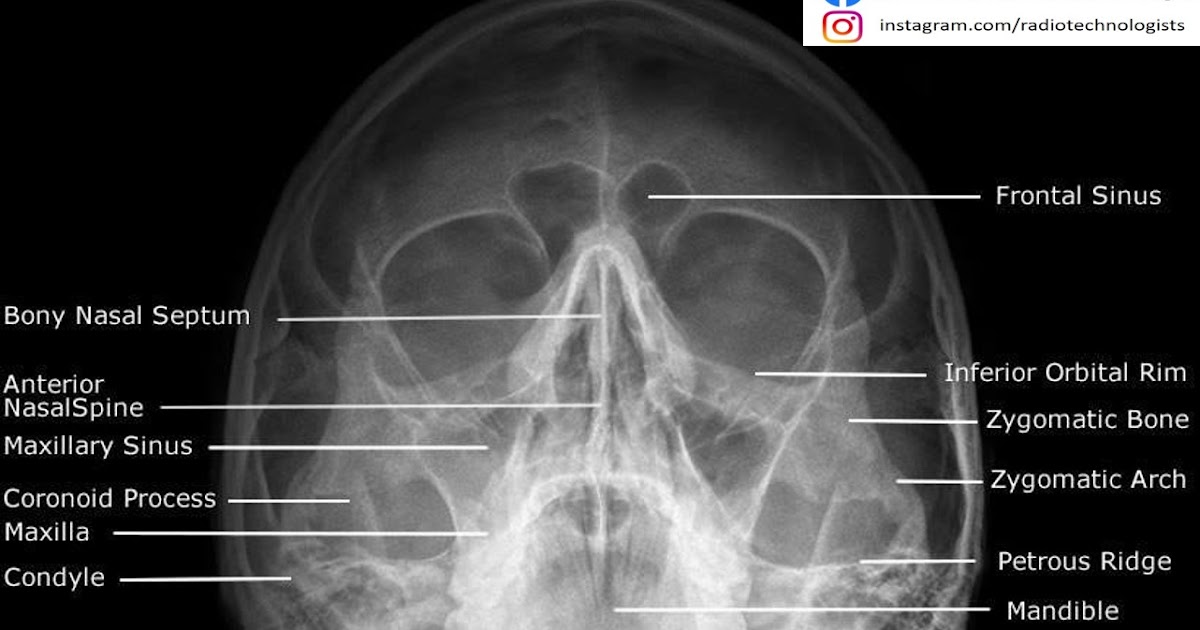

الاشعة العادية على الجيوب الانفية P N S أخصائي تصوير اشعة